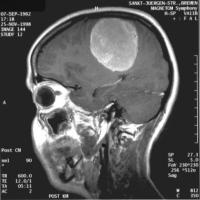

Als Vorgeschmack einige Bilder zum zukünftigen Inhalt: